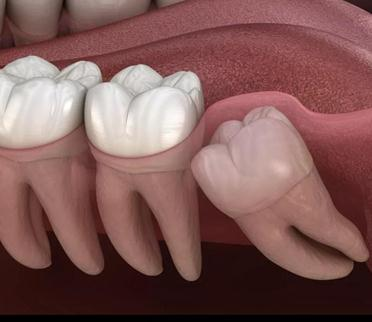

智齿无法正常萌出会有哪些危害?

1.反复发作的智齿冠周炎

阻生的智齿牙冠周围软组织与牙齿之间形成一盲袋,引起食物、细菌的积存,抵抗力下降时,往往会引起智齿冠周炎,严重者甚至会导致间隙感染,全身发热等症状。

2.龋齿

位置不正的智齿与第二磨牙之间容易积存食物残渣,而且不易清洁,长此以往容易形成龋齿,直接破坏牙体组织。

最有效的解决方式首选拔除智齿,但一般由于智齿位置较深,生长方向往往不正常,并且智齿牙根的变异情况比较复杂,所以智齿的拔牙难度和拔牙创伤都会比较大。所以拔除智齿最好采用微创拔牙,以减少拔牙创伤,加快拔牙效率。